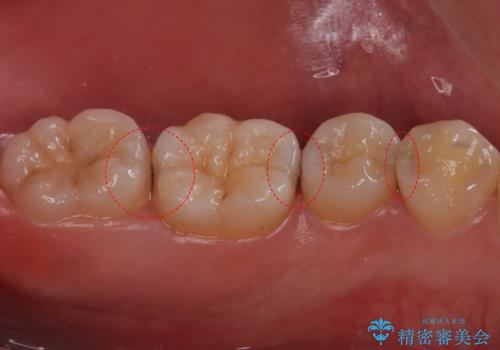

銀の詰め物を除去した後、その奥にある古い詰め物も除去し完全にむし歯を取り切ったことを確認してからセラミッククラウンを装着していきます。

- 右上67 仮歯+ジルコニアクラウン:11,000+110,000円 右上7/根管治療:保険 ファイバーコア:22,000円費用は治療当時の料金となります

詰め物の除去後、残った歯が薄い場合は今後の破折リスクを考慮して被せ物での修復処置を提案することがあります。